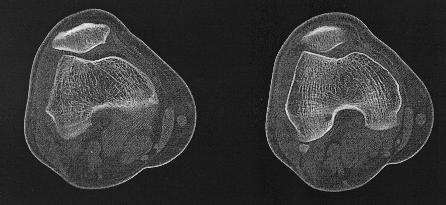

CT van het skelet

Een Ct-scan van het skelet wordt uitgevoerd wanneer er een verdere evaluatie nodig is van een letsel dat gezien is op een klassieke foto. Denk aan fracturen, luxaties e.d., maar ook aan metastasen, artrose,…Zo kan het bijvoorbeeld zijn dat een letsel niet duidelijk genoeg voorkomt op de foto’s en dat er dus twijfel bestaat. Maar ook kan het zijn dat een CT-scan noodzakelijk is om een duidelijk beeld te verkrijgen van een uitgebreide fractuur, om verdere behandeling te bepalen.

Dankzij de moderne computertechnieken is het niet alleen mogelijk om axiale beelden te maken. (lees schijfjes dwars op het lichaam) Maar ook om die beelden te reconstrueren tot een 3D-model. Dit geeft vaak een duidelijk beeld van het bot en zijn letsel.